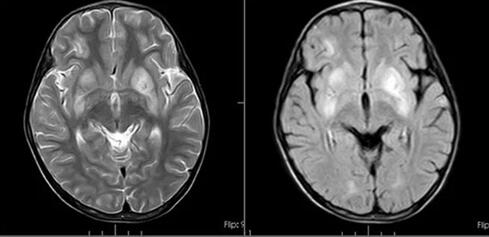

住院期间,我院头颅MR检查回报:双侧基底节区、双侧额叶及左侧颞顶叶多发病变,脑膜可疑强化。视频脑电图结果:1.背景节律异常;2.癫痫样放电,右侧中央区及CZ。

图 我院核磁检查影像

结合检查结果,患儿脑电图有癫痫发电,但无临床发作事件,肢体阵发性强直及扭转痉挛考虑为基底节受累所致肌张力障碍,需早期病因、对症处理,避免疾病进展。